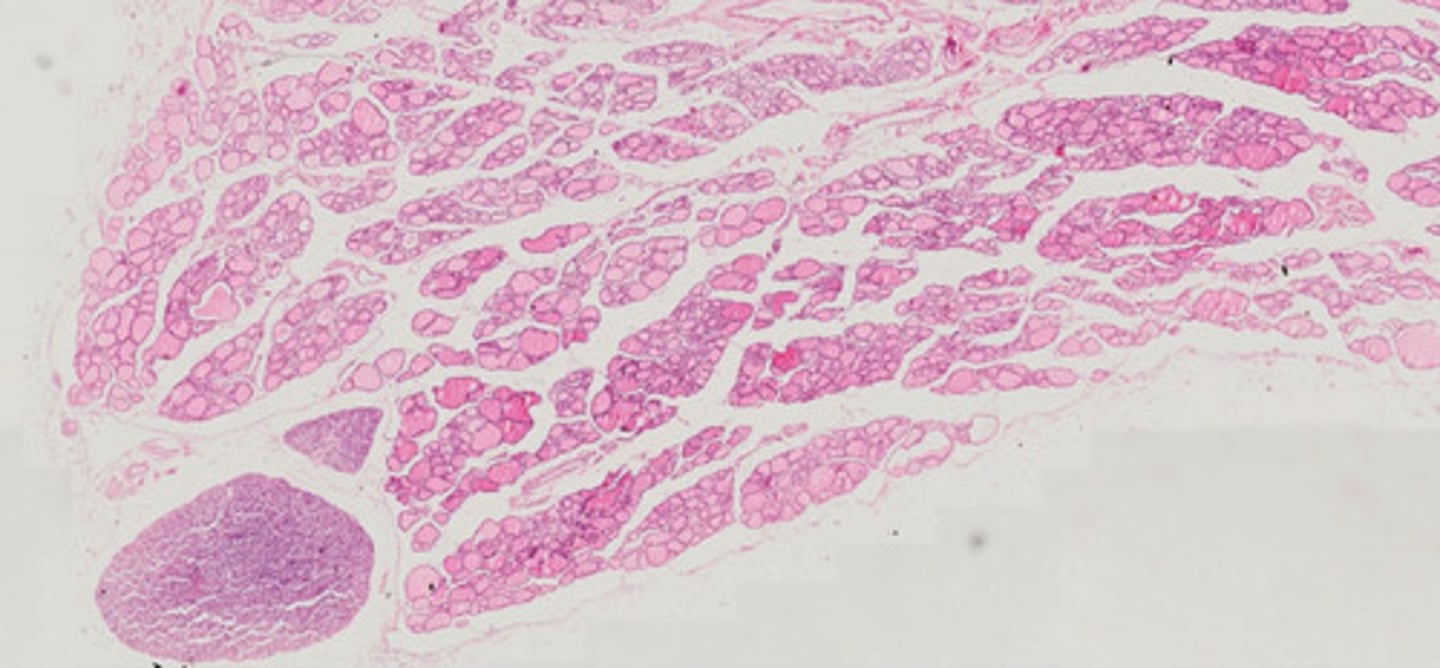

Miąższ płucny (H+E)